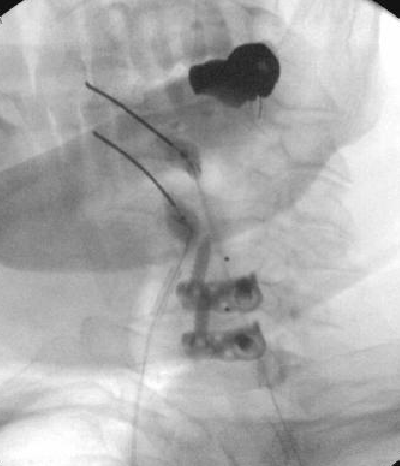

Nasty neuritis. This is 80 degrees 90 seconds.

These images look great. Sorry it happened? Steroid?

Lyrica Rx sent in, and we're starting it for chronic pain (and neuritis). She gets a shoulder scope in two weeks for a large RCT. I like antineuropathics (gabapentin 100mg HS or BID) perioperatively in general. I wish they were given 2 weeks before and after ALL orthopedic surgeries.

Dexamethasone given before RFA needles were removed.